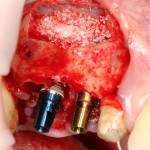

Конечная цель операции синуслифтинга – создание адекватных условий для установки имплантов. При этом, нередко удается провести имплантацию одновременно с операцией синуслифтинга. Как уже говорилось выше, это возможно, если существующий объем костной ткани позволяет стабилизировать имплантат заданного размера (рис 43, 44, 45):

Рисунок 43, 44, 45. Установка имплантов одномоментно с операцией синуслифтинга: слева – этап синуслифтинга, в центре – подготовка лунки под имплантат (виден спейсер и слизистая оболочка гайморовой пазухи), справа – установленный имплант

Оптимальное расстояние от дна гайморовой пазухи до верхней точки альвеолярного гребня верхней челюсти, при котором возможна стабилизация импланта длиной 10-11 мм – не менее 3-4 мм. Однако, в некоторых случаях имплантат длиной 11 мм удается стабилизировать в меньшем объеме костной ткани (рис 46, 47, 48):

Рисунок 46, 47, 48. Стабилизация импланта при толщине костной ткани менее 3 мм: слева – установка импланта после синуслифтинга, в центре – заполнение субантрального пространства спейсером, справа – рентгенологический контроль.